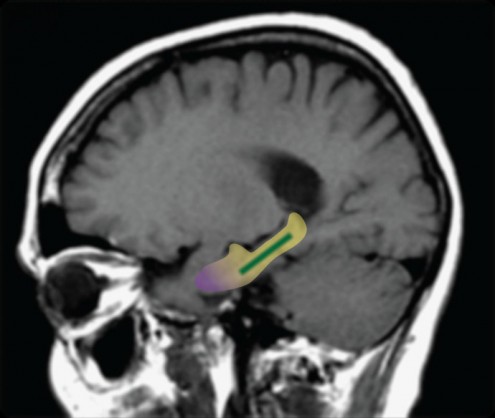

Η περιοχή του εγκεφάλου με κίτρινο χρώμα είναι ο ιππόκαμπος – η οδοντωτή έλικα (σ.σ. pentapostagma.gr – dentate gyrus) εμφανίζεται με πράσινο χρώμα και ο ενδορινικός φλοιός με μωβ χρώμα (Φωτογραφία από το Δελτίο Τύπου).

Ο κύριος στόχος του πειράματος ήταν να μελετηθεί η οδοντωτή έλικα του εγκεφάλου – το μέρος του εγκεφάλου που ευθύνεται για τον σχηματισμό της μνήμης, και είναι ευαίσθητο στην ηλικία. Έτσι, οι επιστήμονες έπρεπε να πραγματοποιήσουν απεικονίσεις του εγκεφάλου για να μετρήσουν τον όγκο αίματος και να αποδείξουν εάν αποτελεί ή όχι την πηγή της συνηθισμένης «αμέλειας» που είναι διαδεδομένη στον πληθυσμό των ηλικιωμένων.